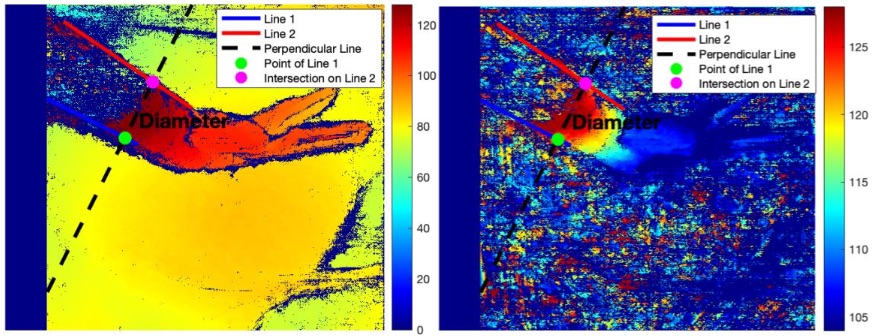

- Disparity Mapping & Depth Recovery: Generated a dense disparity map and back-projected image points to compute real-world 3D coordinates.

- Quantitative Tool Analysis: Estimated the physical diameter of a surgical tool (∼7.53 mm) directly from the reconstructed point cloud using geometric analysis, achieving 95% accuracy.

✅ Demonstrated the full stereo vision pipeline from calibrated image pairs to quantitative 3D metric extraction in a surgical context — achieving 95% accuracy in depth estimation.